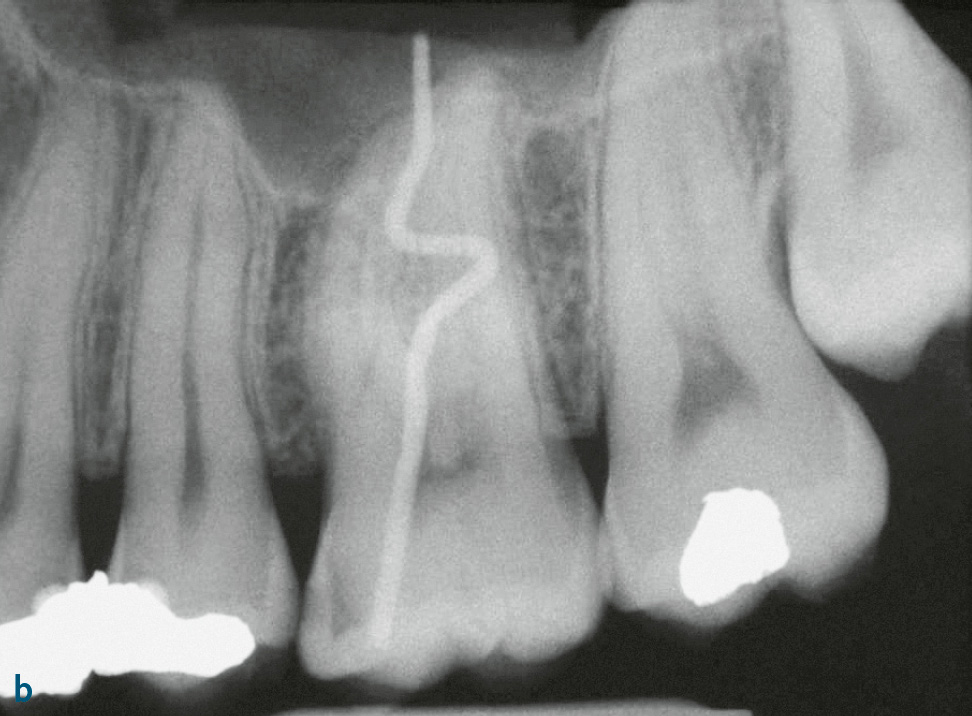

Die Differenzialdiagnose zwischen primär endodontaler Läsion bei partieller Pulpanekrose und tiefer primär parodontaler Läsion, die zu einem Parodontalabszess geführt hat, ist diffizil. Hilfreich ist es, bei der Röntgendiagnostik einen röntgenopaken Stift (z. B. Guttaperchapoint) in die Fistel/parodontale Tasche einzuführen (Abb. 7c, 8). So lässt sich häufig der Ursprung der Eiterung (z. B. periapikale Region) darstellen. Hinweise für eine primär endodontal verursachte Läsion sind kariöse Läsionen (Abb. 8b) oder pulpanahe Restaurationen und Kronen2. Bei etwa 10 % der Kronen kommt es in den ersten 10 Jahren nach Präparation zu Pulpanekrosen. Bei einem Patienten, der generell keine oder wenig Attachmentverluste oder Knochenabbau und nur isoliert an einer Stelle eine stark erhöhte Sondierungstiefe mit Suppuration aufweist (endodontal-parodontale Läsion ohne Beschädigung der Wurzel bei Patienten ohne Parodontitis: Grad 1), sprechen die Befunde für eine primär endodontale Läsion (Abb. 7c, 8). Ein Patient, der auch an anderen Stellen lokalisiert oder generalisiert tiefe Taschen sowie Knochenabbau zeigt, bei dem aber der Beschwerden bereitende Zahn endodontisch nicht vorgeschädigt ist, hat mit hoher Wahrscheinlichkeit eher ein primär parodontales Problem. Eine periapikale hypodense (radiotransluzente) Zone auf zweidimensionalen Röntgenbildern muss kein eindeutiger Hinweis auf eine Läsion primär endodontaler Genese sein. Die dreidimensionale Ausdehnung primär parodontaler Knochentaschen kann je nach Projektion periapikale Osteolysen vortäuschen (Abb. 9).

Abb. 8a, b Jugendlicher Patient mit Beschwerden an Zahn 26. Klinisch findet sich mesiobukkal 26 eine Sondierungstiefe von 11 mm mit Suppuration; der Zahn reagiert positiv auf Sensibilitätstest. Ein Vorbehandler hatte bereits die Diagnose Parodontalabszess gestellt und ein subgingivales Scaling durchgeführt, bevor er zur systematischen Parodontalbehandlung überwies. a) Panoramaschichtaufnahme: kein Anhalt auf Knochenabbau; b) Zahnfilm 26 mit Guttaperchapoint in der mesiobukkalen Tasche: mesial bis ins Dentin reichende Karies, der Guttaperchapoint reicht bis in die periapikale Region. Diagnose: akute Parodontitis periapicalis ausgehend von partieller Pulpanekrose an 26. Die Chance für ein Reattachment nach Wurzelkanalbehandlung war allerdings durch das subgingivale Scaling vergeben worden.